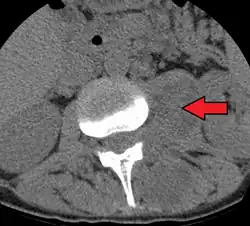

Paraspinal abscess in the psoas muscle